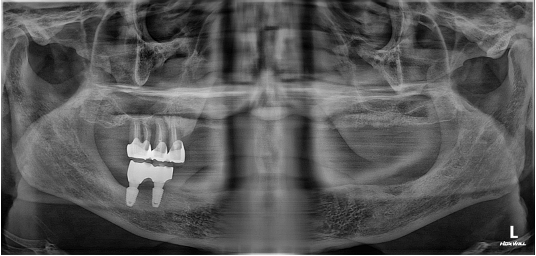

뼈와 임플란트가 떨어진 경우

기존 임플란트를 제거합니다.

뼈가 남아 있는 경우에는 더 굵은 직경의 임플란트를 식립하며 뼈가 없는 경우에는 뼈이식을 진행합니다. 뼈이식 후 임플란트를 재식립합니다.

골조직이 1/2 이하인 경우

기존 임플란트를 제거 후 뼈이식을 통해 골재생 염증 치료 후 상태에 따라 치료 여부를 결정합니다.